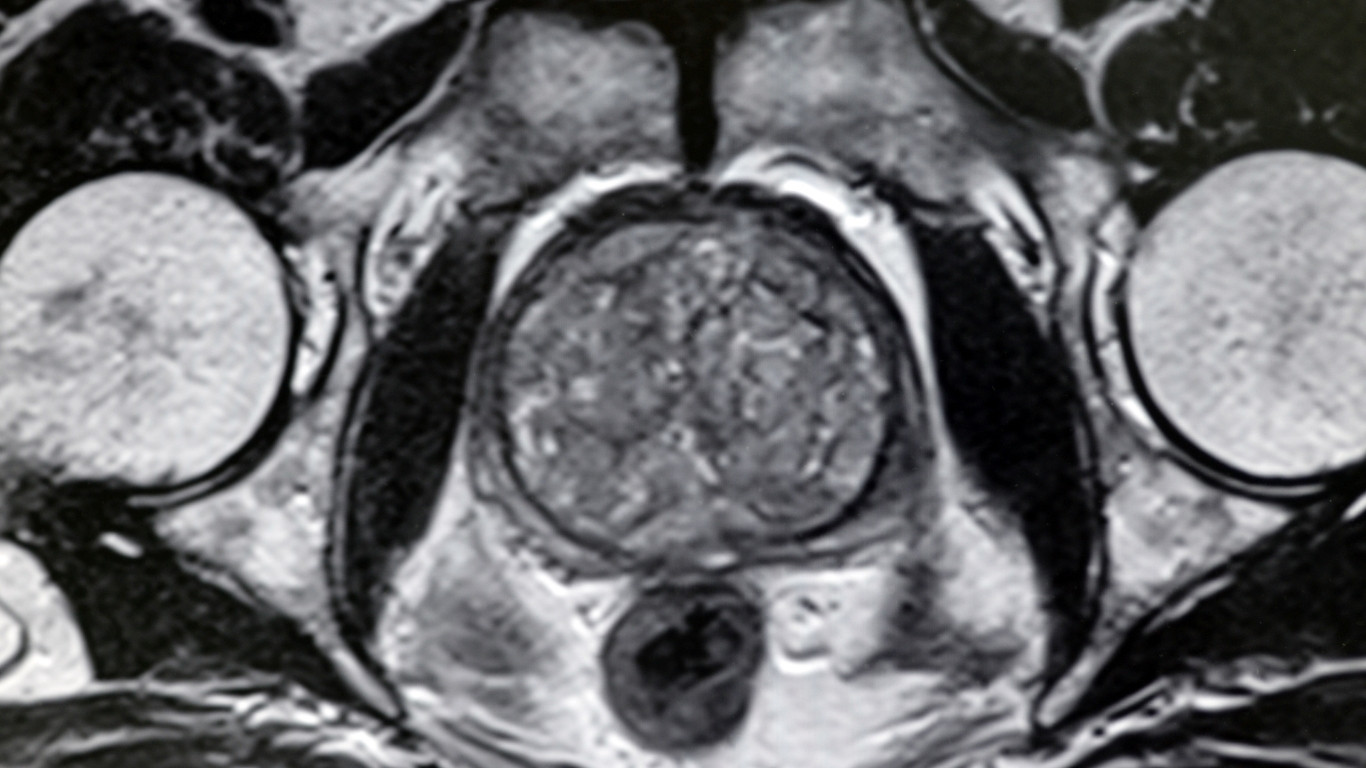

Tăng sinh tuyến tiền liệt (còn gọi là phì đại lành tính tuyến tiền liệt) là tình trạng tuyến tiền liệt to lên theo tuổi, gây chèn ép vào niệu đạo và bàng quang, dẫn đến rối loạn tiểu tiện. Đây là bệnh lý phổ biến ở nam giới trung niên và lớn tuổi, đặc biệt sau 50 tuổi.

Siêu âm bụng hoặc siêu âm qua trực tràng:

Đánh giá kích thước tuyến (bình thường khoảng 20–25 gram).